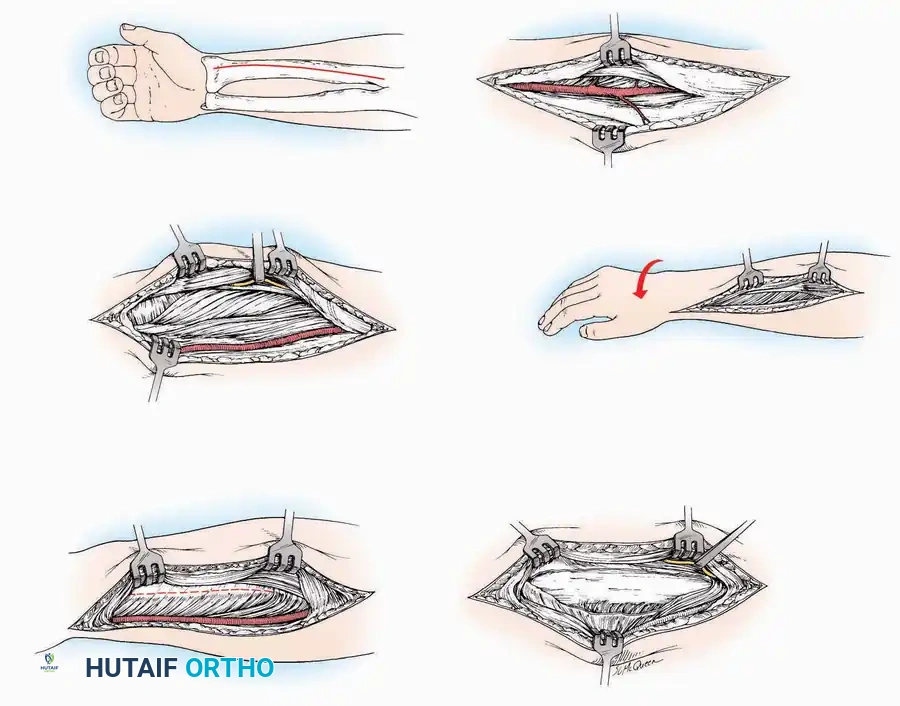

SURGICAL APPROACHES TO THE TARSUS AND ANKLE

Anterolateral Approach

The anterolateral approach is widely considered the "universal incision" for the foot and ankle. It provides unparalleled access to the ankle joint, the talus, and the majority of the tarsal articulations, while safely avoiding the major anterior neurovascular bundle. The only tarsal joints inaccessible via this route are the naviculocuneiform joints (specifically the medial and intermediate).

Indications: Total talectomy, triple arthrodesis, ankle arthrodesis, and open reduction of complex talar neck fractures.

Surgical Technique:

* Incision: Begin over the anterolateral aspect of the leg, medial to the fibula and 5 cm proximal to the ankle joint line. Carry it distally over the joint, crossing the anterolateral aspect of the talar body and the calcaneocuboid joint, terminating at the base of the fourth metatarsal.

* Superficial Dissection: Incise the superficial fascia and the superior and inferior extensor retinacula down to the periosteum of the tibia and the ankle joint capsule.

* Vascular Ligation: This trajectory usually requires the identification and ligation of the anterolateral malleolar and lateral tarsal arteries.

* Nerve Protection: Retract the skin edges carefully. Identify and protect the intermediate dorsal cutaneous branches of the superficial peroneal nerve (SPN), which frequently cross the distal aspect of this incision.

* Muscle Management: Identify the origin of the extensor digitorum brevis (EDB) muscle on the lateral calcaneus. Divide it in the direction of its fibers, or detach its origin entirely and reflect it distally to expose the subtalar and calcaneocuboid joints.

* Deep Exposure: Retract the extensor digitorum longus (EDL) tendons, the dorsalis pedis artery, and the deep peroneal nerve (DPN) medially. Incise the anterior ankle capsule to expose the tibiotalar joint.

* Tarsal Exposure: Expose the talonavicular joint by dissecting deep to the extensor tendons and incising its capsule transversely. Continue laterally through the capsule of the calcaneocuboid joint. By excising the fat pad within the sinus tarsi (lateral and inferior to the talar neck), the posterior facet of the subtalar joint is brought into direct view.

Anterior Approach

Indications: Total ankle arthroplasty (TAA), anterior ankle arthrodesis, and excision of anterior tibial/talar osteophytes (anterior impingement).

Surgical Technique:

* Incision: Make a 10 to 15 cm longitudinal incision over the anterior aspect of the ankle, centered exactly midway between the medial and lateral malleoli.

* Superficial Dissection: Incise the superficial fascia. Identify and protect the superficial peroneal nerve branches laterally and the saphenous nerve medially.

* Internervous Plane: The deep dissection exploits the plane between the Extensor Hallucis Longus (EHL) tendon (innervated by the deep peroneal nerve) and the Extensor Digitorum Longus (EDL) tendons (also innervated by the deep peroneal nerve).

* Neurovascular Bundle: Incise the extensor retinaculum. Carefully identify the anterior tibial artery and the deep peroneal nerve, which typically lie between the EHL and EDL, or directly deep to the EHL. Retract the neurovascular bundle laterally with the EDL, or medially with the EHL, depending on the specific anatomical variant encountered (lateral retraction is most common).

* Capsulotomy: Incise the anterior joint capsule longitudinally. Elevate the capsule subperiosteally from the anterior tibia and the talar neck to expose the entire tibiotalar articulation.